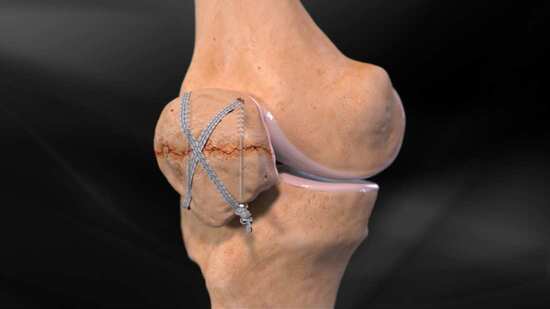

![]() Kneecap Fractures (Patella Fractures): Fixation With Screws and Braided Suture Animation 1m  |

![]() Kneecap Fractures (Patella Fractures): Fixation With a Plate and Screws Animation 1m  |

Kneecap Fractures (Patella Fractures): Fixation With a Plate and Braided Suture